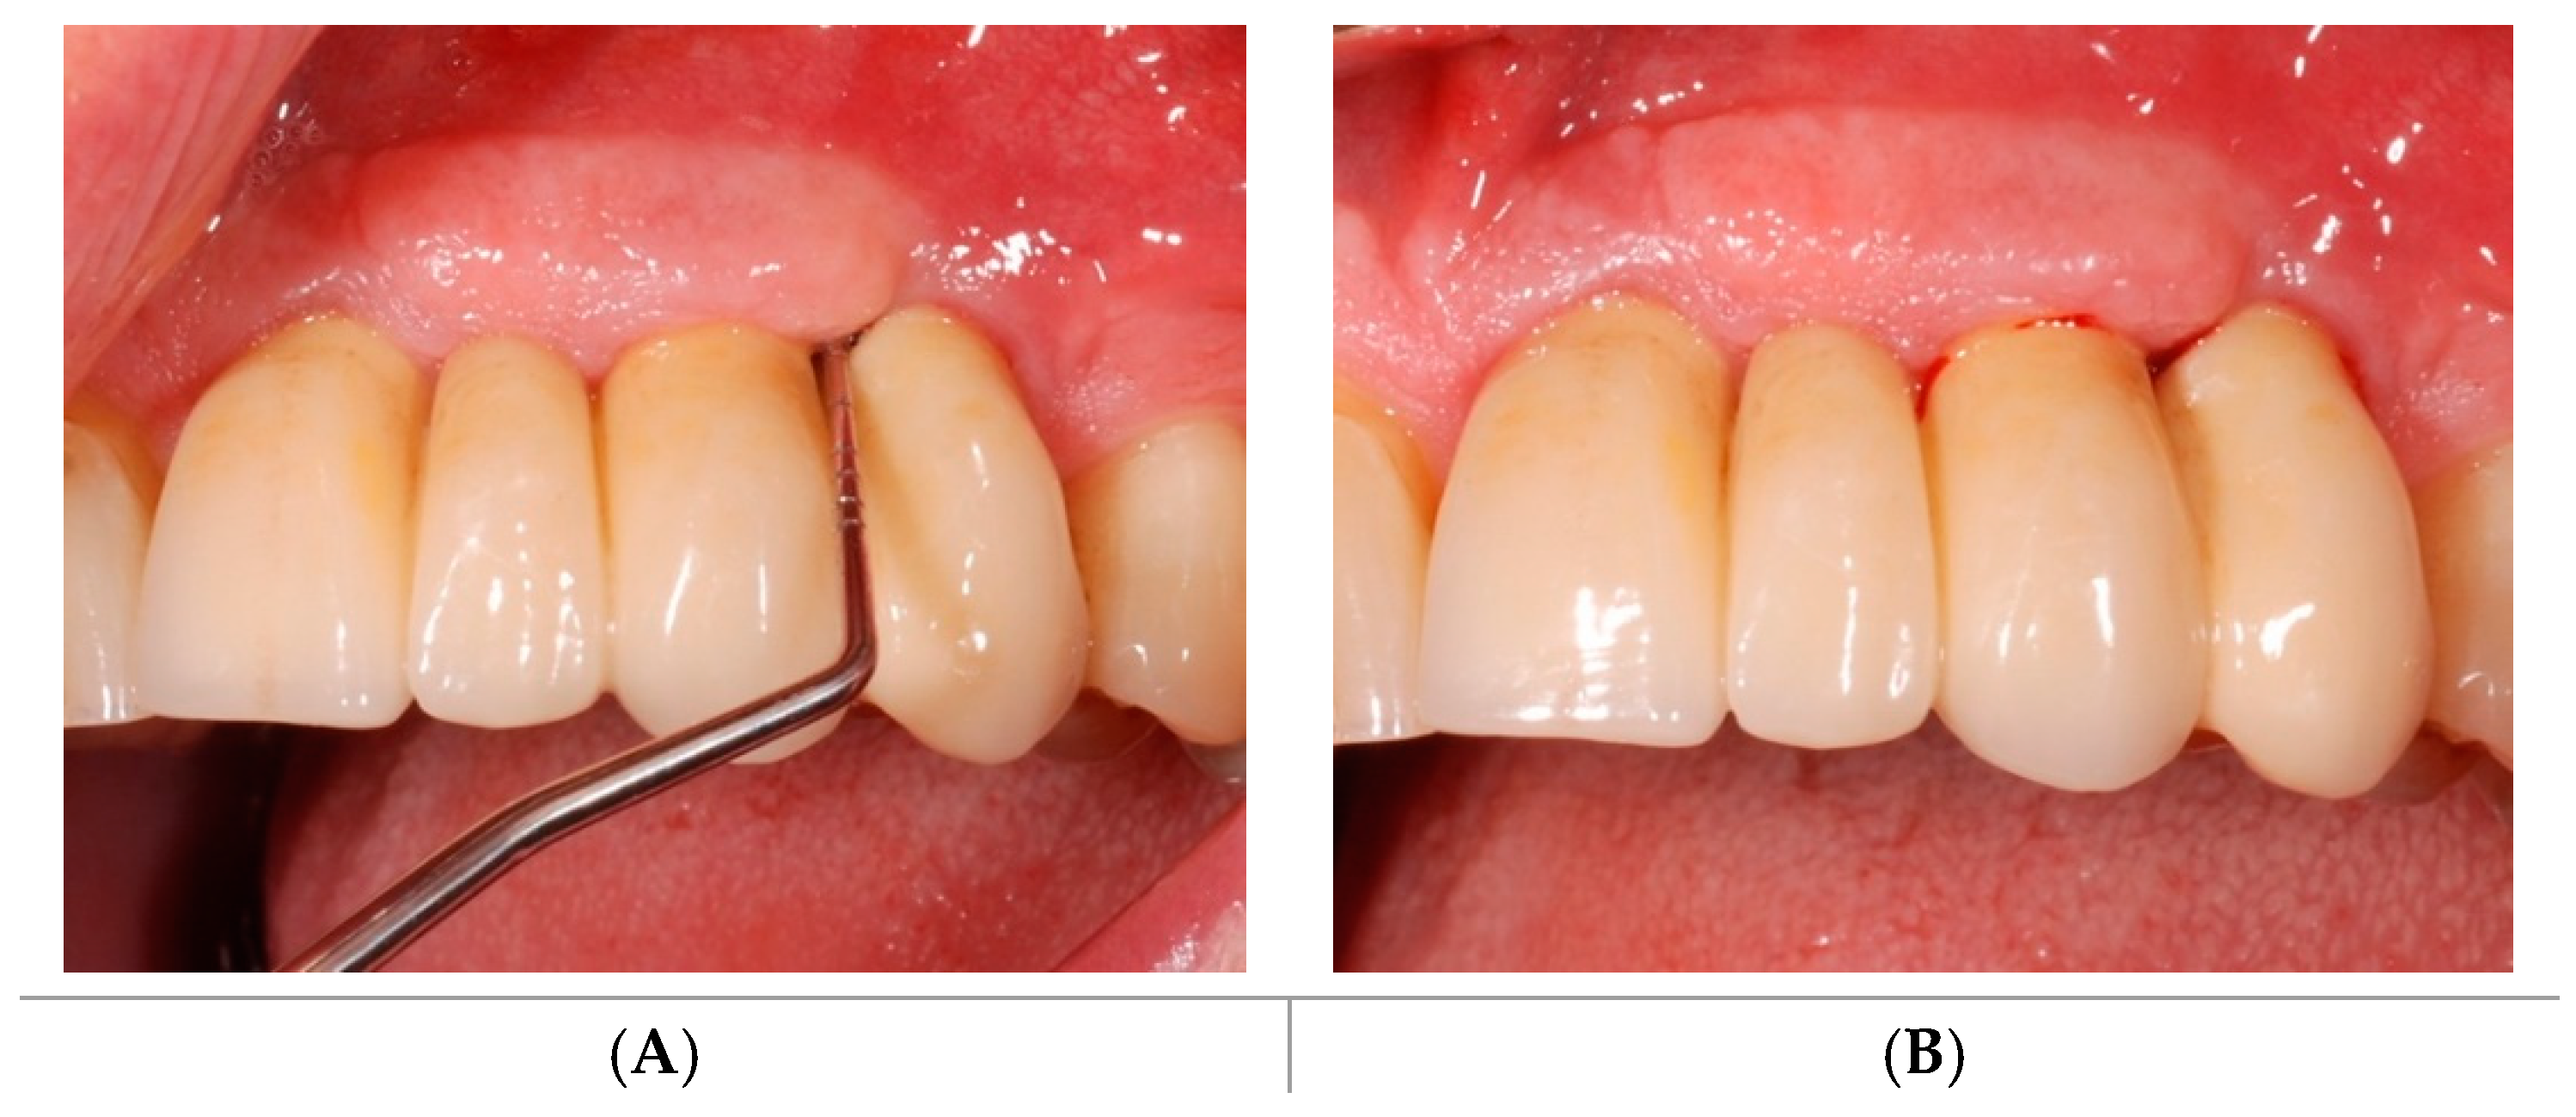

2.1. Demographics

2.2. Clinical Outcomes

4. Materials and Methods

4.1. Study Design

4.2. Soft Tissues Assessment

4.4. Study Protocol and Treatment

4.5. Test Substances and Administration